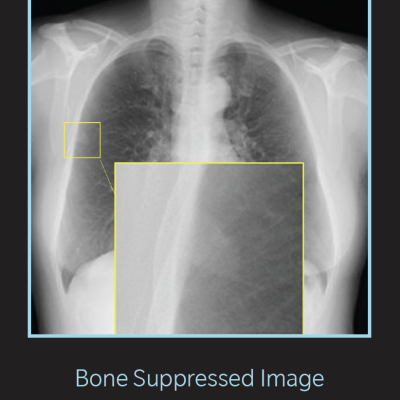

Bone-suppressed image (Photo: Konica-Minolta Healthcare)

Konica Minolta’s BSI suppresses the ribs and the clavicle from standard chest radiographs to enable clearer visualization of the lung and reveal soft-tissue details that may otherwise remain obscured. By improving the visibility of lung structures — even in dense or complex regions — BSI enhances diagnostic clarity and the radiologist’s confidence in identifying subtle findings such as nodules, interstitial markings, consolidations or early signs of pathology.